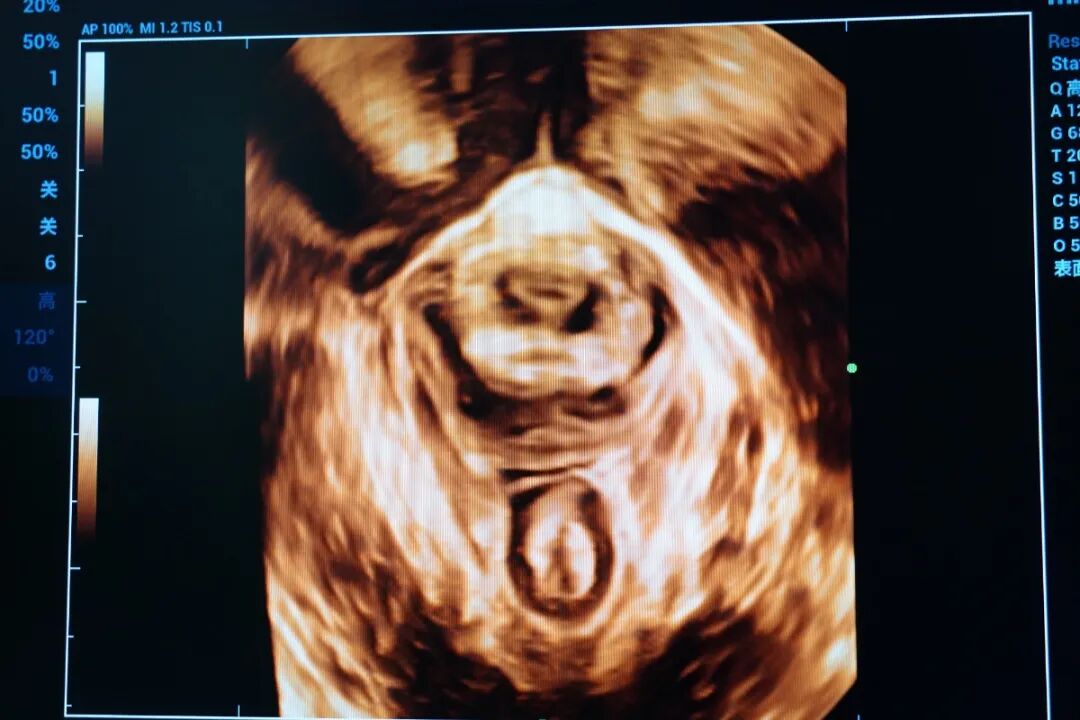

子宮三維超聲下診斷的完全性縱膈子宮合并子宮內(nèi)膜息肉

◆宮內(nèi)節(jié)育器的診斷:三維超聲的透明模式可以清晰地顯示節(jié)育器的形態(tài)、位置。對一些節(jié)育器異常的情況,如肌層內(nèi)嵌頓、斷裂、位置改變等都有幫助。

子宮三維超聲下觀察節(jié)育環(huán)